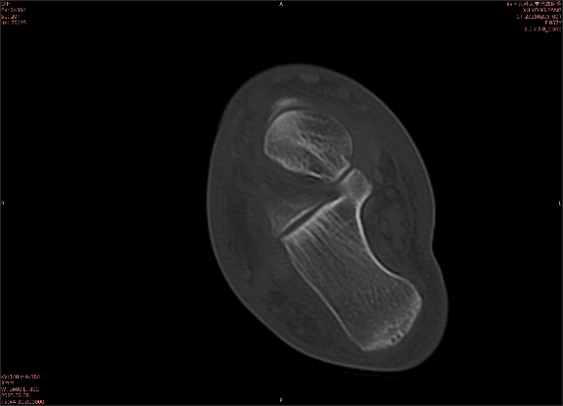

舉例圖像

圖1

專業(yè)解釋看不懂沒關(guān)系,大家看圖1和圖2就可以了,這是同一個(gè)患者跟骨的磁共振和CT圖像,圖1的紅色箭頭指示的黑線就是磁共振圖像顯示的骨折線,一目了然。而對比圖2的CT圖像上并未顯示異常。